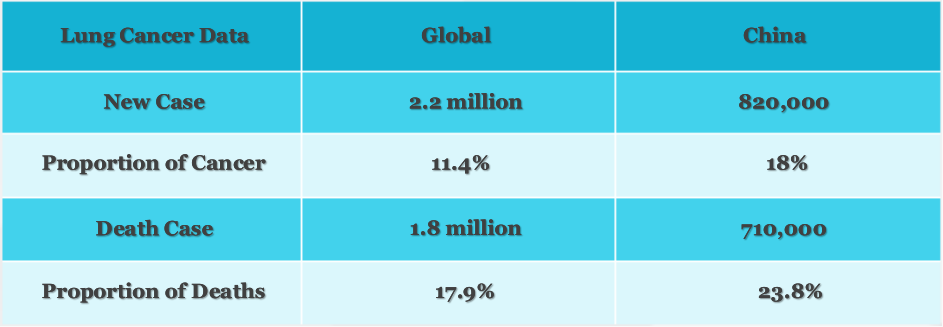

According to the relevant data of the International Agency for Research on Cancer (IARC) of the World Health Organization (WHO), lung cancer has become one of the most serious malignant tumors, and the prevention and treatment of lung cancer has become the top priority of cancer prevention and treatment.